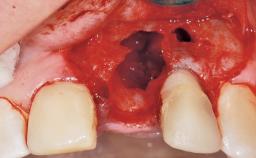

Late Placement of an Implant in a Maxillary Left Central Incisor Site

A 30-year-old female patient had lost tooth 21 and was referred to our clinic for consultation and treatment. Due to advanced apical infection, tooth 21 had been extracted two months earlier at another clinic and an acrylic-resin tooth had been bonded to the adjacent teeth. The patient desired implant treatment to avoid any damage to the adjacent natural teeth. While the patient had no history of any systemic disorder, she was a heavy smoker and exhibited medium to advanced periodontitis in the entire jaw. After the initial treatment to achieve a pocket probing depth of less than 4 mm and no bleeding on probing, a decrease in the height of the papillae mesial and distal to the extraction site and overall gingival recession were observed.

Soft Tissue Anatomy Intact Defective